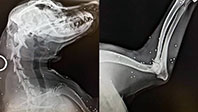

Köpeğin Vücudunda Çok Sayıda Saçma

Köpeğe ait röntgen filminde ise baş, boyun, kol, göğüs ve bacak kısımlarında çok sayıda saçma tespit edildi. Hayvan hastanesi tarafından jandarmaya verilmesi için bir de rapor tutuldu. Raporla birlikte jandarma karakoluna giden Tuncay Şengül, köpeğine zarar veren M.U.’dan şikayetçi oldu. Olay günü köpeğin hiçbir canlıya zarar vermemesine rağmen av tüfeğiyle vurularak ciddi yaralar almasının hiçbir şekilde açıklanamayacağını belirten Şengül, “Kimseye zarar vermedi bu zaman kadar. Bahçeyi temizlemek için açmıştık ama yan komşunun alanına geçmiş. Köpek oyun amaçlı tavuk ve kazların arkasından koşmuş o da ölmesini istediği için direkt sıkmış. Köpeğin yanında olsaydık belki bizi de vururdu. Hayvanı sevmeyen insanı da sevmez. Elinde silah görmedim ama ‘Ben vurdum’ dedi” diye konuştu.